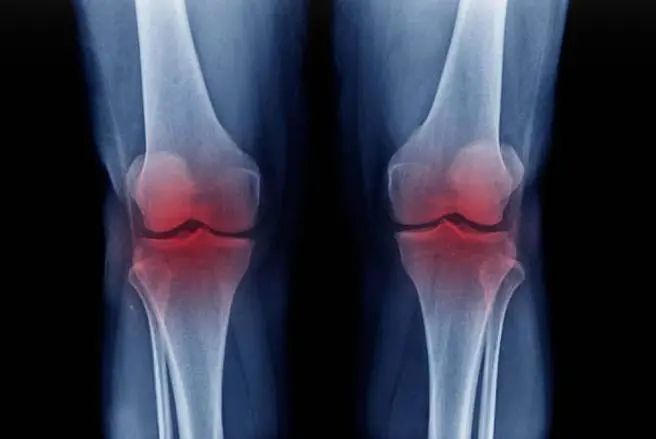

膝關(guān)節(jié)是人體重要的大關(guān)節(jié)之一,對于維護(hù)人體的平衡與運(yùn)動能力發(fā)揮著關(guān)鍵作用。然而,膝關(guān)節(jié)的退行性改變和損傷治療一直是醫(yī)療領(lǐng)域的一個挑戰(zhàn)。最近,美國俄亥俄州的新聞網(wǎng)站 cleveland.com報(bào)道了一個關(guān)于干細(xì)胞療法如何幫助三位膝關(guān)節(jié)損傷患者恢復(fù)關(guān)節(jié)功能的案例,這些患者因此避免了進(jìn)行外科手術(shù)治療

關(guān)節(jié)退行性變和由此引起的關(guān)節(jié)炎是導(dǎo)致全球殘疾的主要病因之一,而膝關(guān)節(jié)受損尤為常見,因其承載了日?;顒拥拇蟛糠謮毫?。傳統(tǒng)的膝關(guān)節(jié)損傷治療方法包括藥物治療、物理治療及膝關(guān)節(jié)置換手術(shù)。盡管如此,藥物治療效果有限,而膝關(guān)節(jié)置換手術(shù)的恢復(fù)期較長,這些限制了治療效果,迫切需要新的無創(chuàng)治療方法。目前,干細(xì)胞治療已為罹患多種病癥的患者帶來了顯著的健康改善,尤其是對于那些因膝關(guān)節(jié)損傷而行動受限的老年人和職業(yè)要求高的工作人員。

干細(xì)胞藥物在骨關(guān)節(jié)炎中的研究及應(yīng)用治療膝關(guān)節(jié)損傷一直是醫(yī)學(xué)研究的重要課題,傳統(tǒng)的膝關(guān)節(jié)置換手術(shù)雖然效果顯著,但長時(shí)間的術(shù)后康復(fù)對患者的工作和生活影響巨大。因此,科研人員一直在尋找更為有效且非侵入性的治療方法。近年來,干細(xì)胞治療作為再生醫(yī)學(xué)的一個研究焦點(diǎn),已在膝關(guān)節(jié)損傷治療中顯示出巨大的潛力。多個實(shí)際案例已經(jīng)證明了干細(xì)胞治療在安全性和有效性方面的優(yōu)勢。國際上,對于膝骨關(guān)節(jié)炎的治療,已有幾種干細(xì)胞藥物被批準(zhǔn)上市。2009年,歐洲批準(zhǔn)了名為Chondrocelect的干細(xì)胞藥物,專門用于治療膝關(guān)節(jié)軟骨的缺損。2012年,韓國通過了間充質(zhì)干細(xì)胞藥物Cartistem的上市申請,該藥物用于治療退行性關(guān)節(jié)炎和膝關(guān)節(jié)軟骨損傷。2016年,美國也批準(zhǔn)了名為Maci的干細(xì)胞藥物,同樣用于治療膝關(guān)節(jié)軟骨損傷。